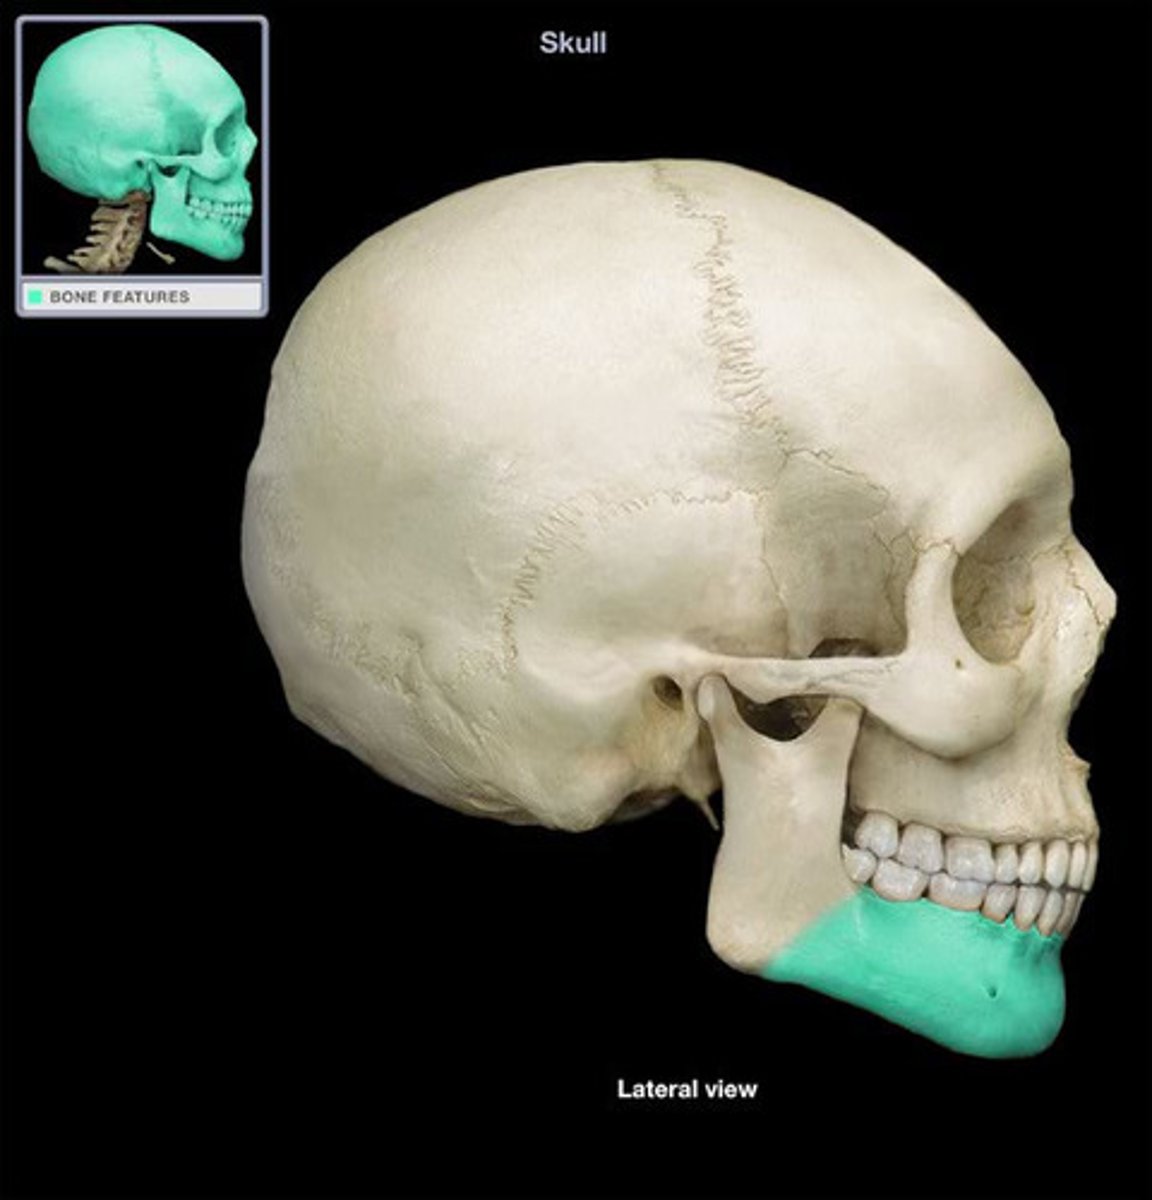

Mandible Body (Mandible)

horizontal portion of the mandible

What is the calvarium?

skull cap, portion of neurocranium consisting of the frontal, parietal and occipital bones

coronal suture

the suture between the parietal and frontal bones of the skull

pterion

Junction of frontal, parietal, sphenoid, and temporal bones. Structural vulnerability as it is thin and middle meningeal artery is just deep, so hard head blow can result in subdural hematoma